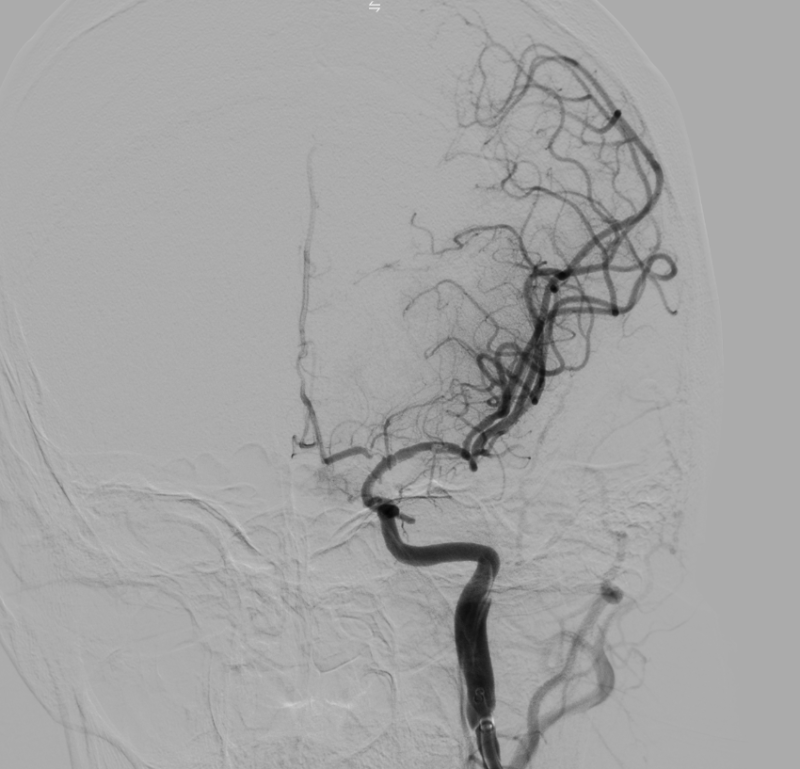

Kết quả chụp DSA xác định tắc động mạch não giữa trái đoạn M1 do hẹp nặng. Kíp can thiệp đã tiến hành nong bóng tái thông mạch máu, khôi phục dòng chảy lên não thành công.

Hình ảnh: DSA sau can thiệp tái thông TICI 3